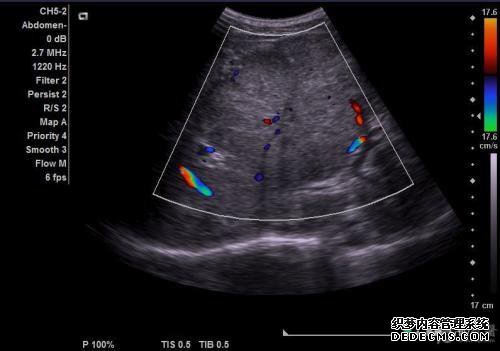

医学CA是什么意思?